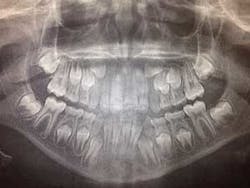

Before you begin treatment, take records. These include photos, x-rays, and diagnostic models. It is important to document the state of the patient prior to treatment. Regarding root resorption, it is essential to take radiographs. Any orthodontic treatment should include pretreatment and post-treatment radiographs that allow visualization of the roots. I recommend panoramic radiographs for this purpose. While it is common in general dentistry to take panoramic x-rays every five years, this is too long for patients in orthodontic treatment. Root resorption can be evident radiographically in as little as six months of orthodontic treatment. Because of this, I take panoramic x-rays every six to eight months in my practice.